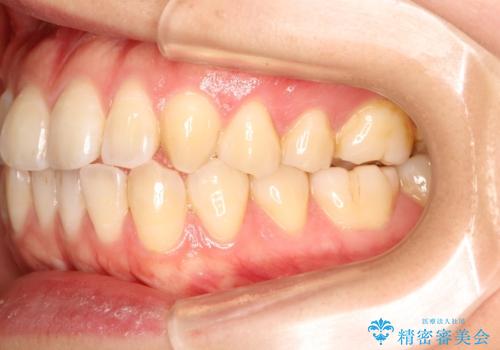

初診時の歯並びの状態としては、上下ともに前歯部に限局した軽度ののがたつき(叢生)がある状態でした。

主に歯列弓の拡大とディスキング(歯と歯の間に隙間を作る処置)を行い叢生を改善しました。